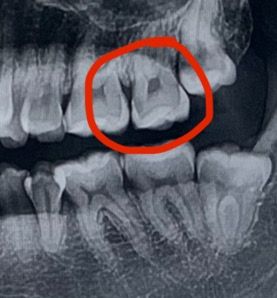

어금니 시 충치치료 인레이? 크라운?

어금니 충치가 깊어 크라운(지르코니아)를 해야 한다고 해서 충치부위 삭제 후 임시로 메꾼 상태입니다. (충치가 신경까지 닿지는 않았으나 인접하다고 하심. 일단 신경치료없이 크라운진행)

임시로 메꾼 치아로 2주 정도 생활 중인데 10번 중 1번 씹을 때 아파요 음식물이 메꾼 곳 틈 사이에 들어가면 아픈 거 같아요 이런 경유 신경치료 필수일까요 ㅠㅠ

• 1번 째 사진

치아 사이에 충치가 잇는거 같습니다. 인레이 치료를 하셔야될것같고 신경치료 가능성도 잇어 보입니다.

사진상으로는 신경치료 가능성이 높지만일단 충치를 제거해본 이후에 결정할 것 같습니다.

지금 사진으로 정확한 판단이 어렵지만 신경치료를 해야할 가능성이 매우 높습니다. 인레이로 가능하다고 하는 치과도 증상이 나타난다면 결국에는 신경치료로 넘어갈 것입니다. 즉 충치가 이미 신경과 매우 근접하므로 신경치료의 가능성을 무조건 염두해두고 치료를 해야 합니다.

현재 임시 치아 상태에서 지속적으로 불편감이 나타나고 개선되지 않는다면 결국에는 신경치료로 넘어갈 가능성은 매우 높습니다.